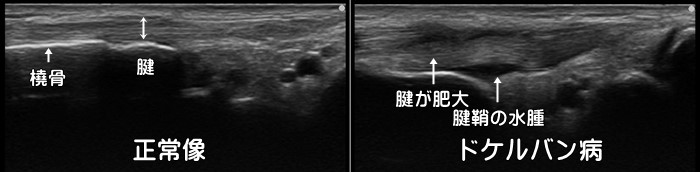

ドケルバン腱鞘炎

手首の親指側の腱鞘炎です。スマートフォンの普及で学生~年配の方まで幅広く見られます。手首を小指側に曲げたり、手首を手のひら側に曲げて親指を大きく開くと痛みが誘発されます。エコーでは腱の周囲の低エコー像(黒)や腱の肥大が確認できます。